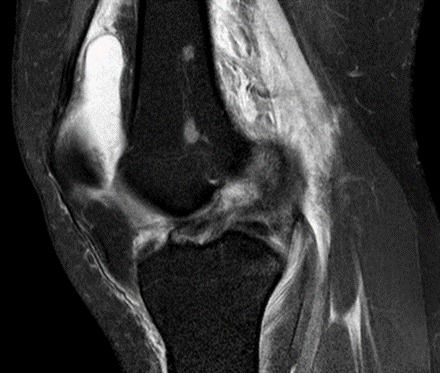

十字韌帶撕裂 - 可以唔做手術嗎?

因為十字韌帶 (Anterior cruciate ligament, 簡稱 ACL) 本身沒有血液供應, 它自己唔會痊癒. 只有少數非常輕微的撕裂可能會自然痊癒.

假如不處理好十字韌帶, 可以導致半月板或軟骨受損, 引致關節發炎. 日後可能會出現更多的關節問題.